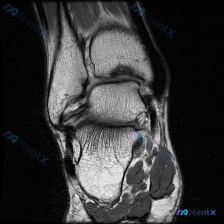

刚看到一份踝关节MRI病例,问题是询问影像上观察到的软骨异常相关发现,整理一下资料和分析思路分享给大家。 病例影像基础信息 这是放射影像-踝关节MRI-T2序列-矢状位,系统评估整体结构如下: 1. 骨与关节:胫距关节间隙正常,关节面轮廓可,距骨穹窿皮质连续,未见明确骨折线或弥漫骨髓水肿;距下关节、...

最近碰到一个很有启发的病例,临床问题是问这张踝关节MRI-T1矢状位影像的观察结果是不是软骨异常,整理一下完整分析思路给大家。 一、影像基本信息 本次仅提供踝关节MRI-T1序列-矢状位单张图像,先把客观阅片结果整理出来: 1. 骨骼结构:胫骨远端、距骨、跟骨、足舟骨及部分楔骨显示清晰,骨皮质连续,...

看到这份踝关节MRI的读片申请,核心问题是排查软骨异常,整理了完整的读片和分析思路分享给大家。 一、影像基本信息 这是一张踝关节MRI轴位T2加权图像,扫描层面为踝关节水平,展示胫骨远端后方、距骨及后踝周围软组织结构: 1. 骨结构:胫骨后缘、距骨体后部轮廓清晰,骨皮质低信号、骨髓中等信号,未见明显...